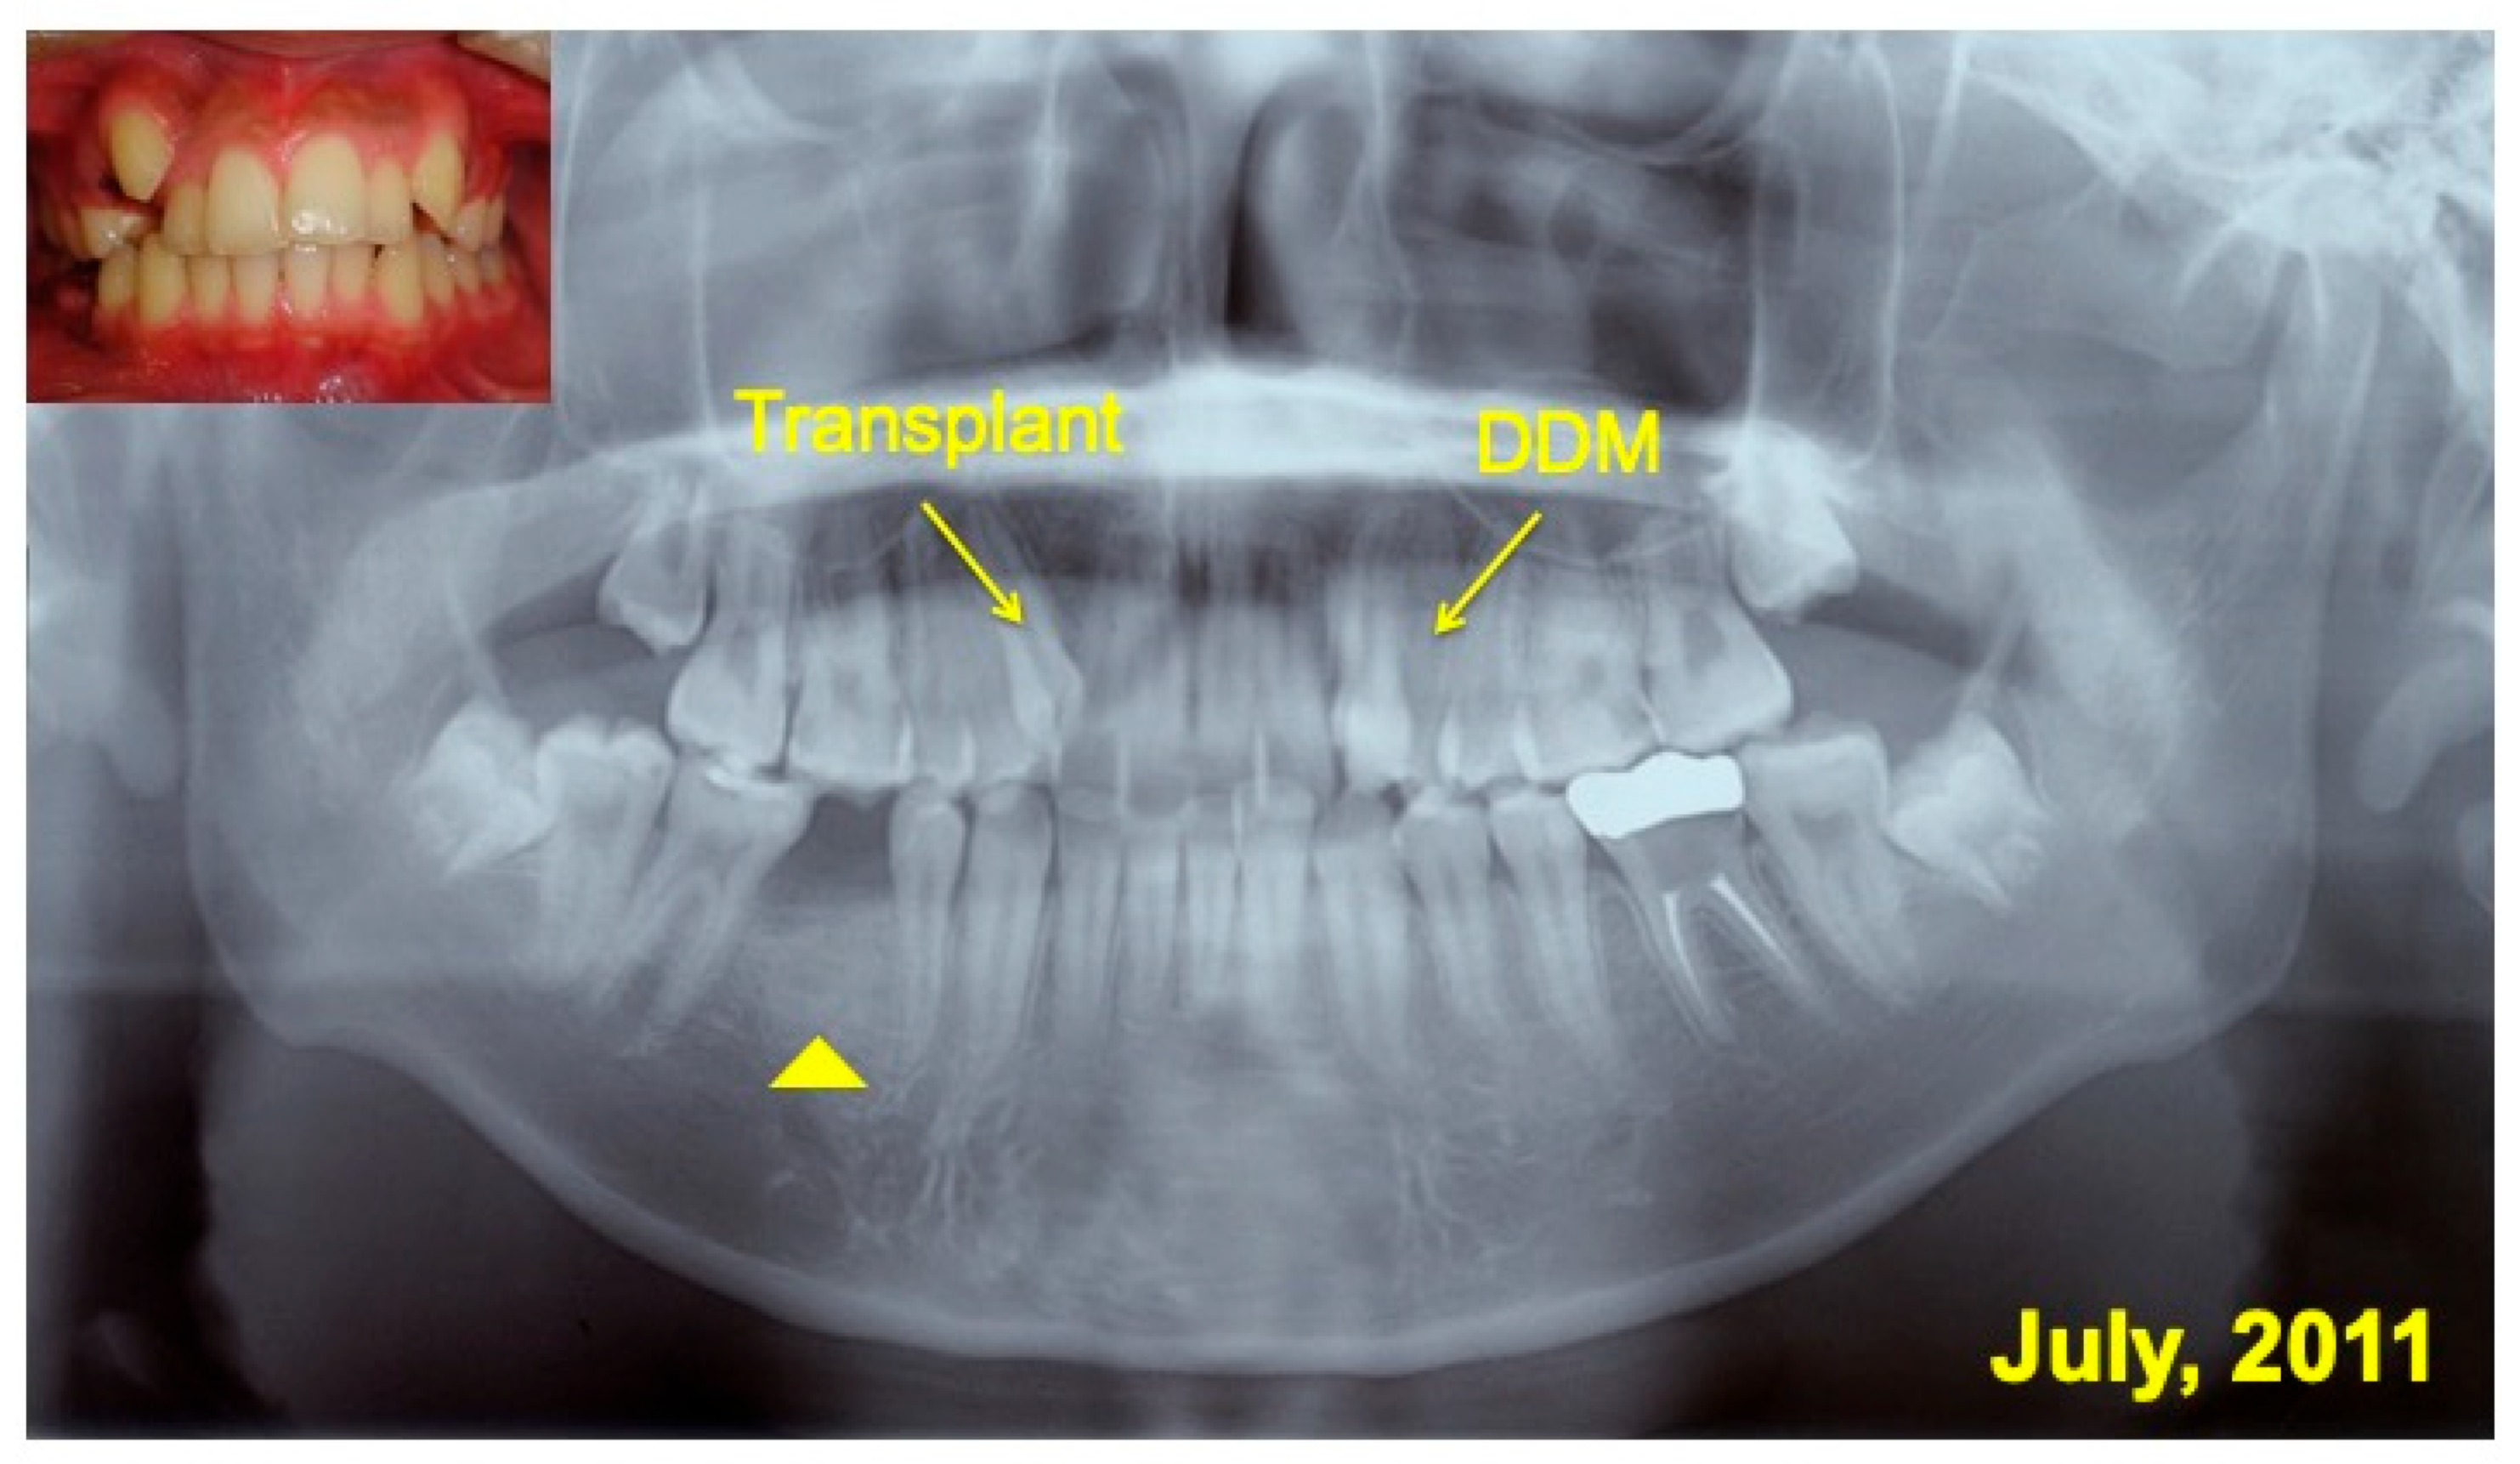

2.1. Clinical Case

2.2. Surgical Planning

3. Results

3.1. Gross View and Examinations after Surgery

3.2. Radiographic Evaluation